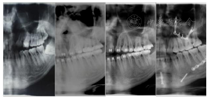

曲面断层片检查(图3-A):B1、B3间骨量不足,牙根远中倾斜,第三磨牙阻生。

CBCT检查(图4):双侧关节头不对称,开闭口、间隙正常。